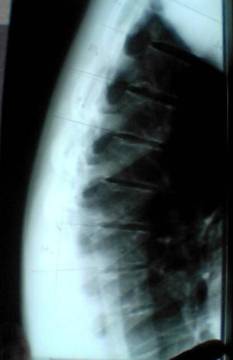

Die Skoliose ist mini. Über den Daumen gepeilt vielleicht 10 Grad. Also nicht der Rede wert.1001 hat geschrieben:1. Was für einen grad habe ich

Die Kyphose ist meines Erachtens nicht ganz drauf, aber ich glaube Du hattest einen Morbus Scheuermann. Ich meine auf dem seitlichen Bild lassen sich Deckplatteneinbrüche erkennen, sog. Schmorlche Knoten. Typisches Symptom für Morbus Scheuermann. Aber da können Dir andere hier sicherlich mehr zu sagen.

Das Röntgenbild ist schlecht weil darauf weder der obere noch der untere Neutralwirbel zu sehen sind, folglich kann man es nicht vermessen!

Eine seitliche WS-Ganzaufnahme im Stehen wäre erforderlich!

Eine deutliche Hyperkyphosierung ist aber sichtbar und die Scheuermann-Zeichen sind sehr deutlich! Lass das von einem erfahrenen Orthopäden bestätigen, ich bin kein Arzt!

Was wir als Scheuermannzeichen auf in dem Bild ansehen, habe ich mal unten markiert. Schau selbst auf dem origiginal Bild nach, ob sich diese Einbuchtungen dort wiederfinden oder ob es Fehler des Bildes sind.1001 hat geschrieben:der Letzten Bericht von einem Orthopäden steht schwarz auf weiss "keine Anzeichen auf Scheuermann..."

Die Bilder sind zwar nicht die brillantesten aber auch ich meine dort Schmorlsche Knötchen zu erkennen.1001 hat geschrieben:Ihr seind zwat keine Ärzte, aber nehmt mich zumindest ernst, eure Ratschläge helfen mir weiter, Danke, der Letzten Bericht von einem Orthopäden steht schwarz auf weiss "keine Anzeichen auf Scheuermann...",